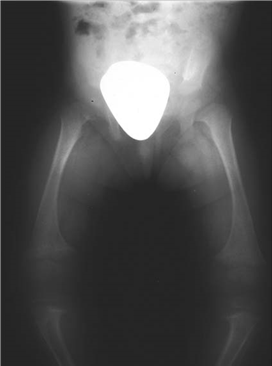

The radiograph above was performed on a child who presented with bowed legs.

What do you think the diagnosis is?

This plain radiograph of the pelvis and knees shows generalized widening of the metaphysis and cupping of the epiphysis in keeping with a metabolic condition such as rickets. Diff erential diagnosis would include a generalized skeletal dysplasia.

What is rickets?

Rickets is a disease of growing bone that is unique to children and adolescents. It is caused by a failure of osteoid to calcify in a growing person. Failure of osteoid to calcify in adults is called osteomalacia.